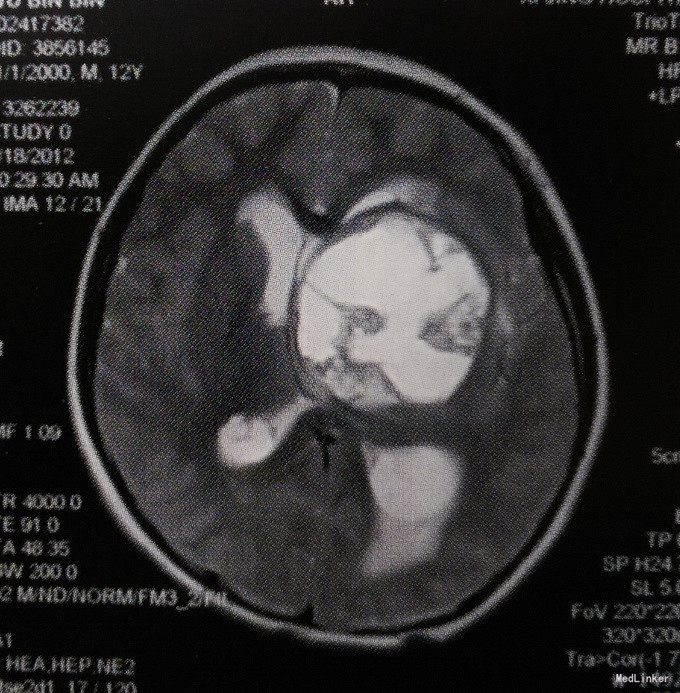

体格检查:意识呈昏睡状,查体不配合,双侧瞳孔等大等圆、对光反射迟钝,四肢肌力III级,肌张力轻度增高,右侧Babinski征阳性,颈抵抗阳性。 头颅MRI检查:左侧基底节区及丘脑占位性病变,呈囊实性混杂成分,边界欠清,实性成分呈明显不均匀强化,考虑生殖细胞瘤或胶质瘤可能性大;左侧侧脑室明显受压变形,中线向右侧移位;幕上梗阻性脑积水。